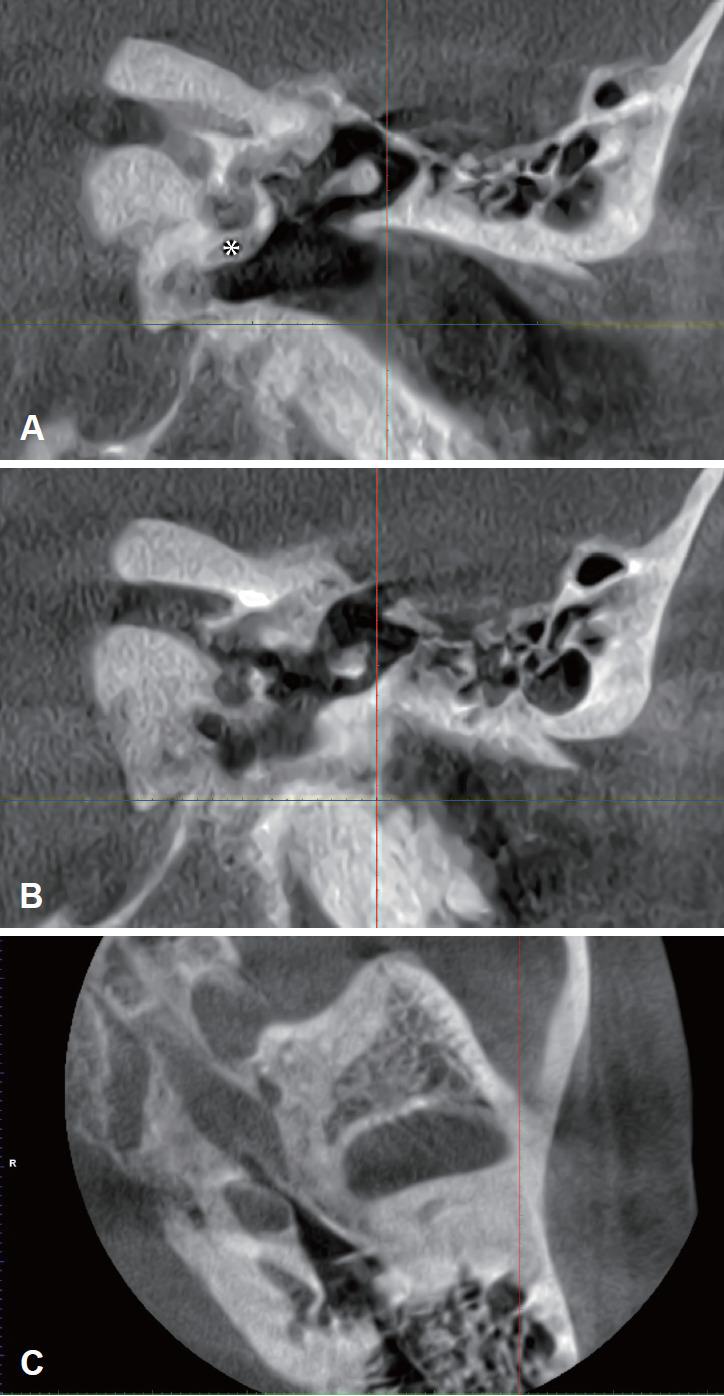

Standard round window (RW) cochlear implantation is a well-described technique. Implantation might be difficult in patients with inner and middle ear anomalies, in some cases because of not achieving adequate exposure to the RW, with a related higher risk of complications such as facial nerve injury. It is proposed a combined microscopic/endoscopic oval window approach in a 63 year old man affected by bilateral Menière disease, with bilateral severe sensorineural hearing loss, speech discrimination score for bysillabic words under 40% and a hidden RW by anomalous facial nerve course. All electrodes entered the cochlear with good freefield thresholds and auditory ability results. A partial marginalis nerve palsy occurred at the second postoperative day and completely reversed at 2 months from surgery. Endoscopicassisted oval window cochlear implantation may be a safe alternative surgical technique in cases where surgeons are not able to access RW.

标准圆窗(RW)人工耳蜗植入是一种已被充分描述的技术。对于患有内耳和中耳畸形的患者,植入可能会很困难,在某些情况下是因为无法充分暴露圆窗,这会带来如面神经损伤等并发症的较高风险。本文报道了一名63岁双侧梅尼埃病患者,伴有双侧严重感音神经性听力损失,双音节词言语辨别得分低于40%,且圆窗因面神经走行异常而隐匿,采用显微镜/内镜联合椭圆窗入路进行人工耳蜗植入。所有电极均顺利进入耳蜗,术后自由声场阈值和听觉能力结果良好。术后第二天出现部分边缘性面瘫,术后2个月完全恢复。在内镜辅助下的椭圆窗人工耳蜗植入可能是外科医生无法暴露圆窗时的一种安全替代手术技术。